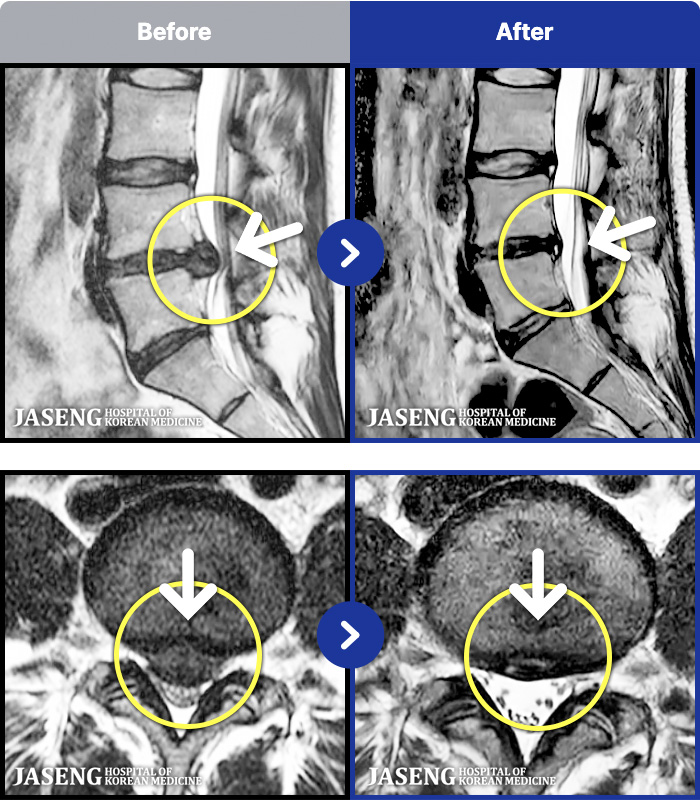

[ϻ] 24.07.25~25.08.01

ȯںп Ǹ ǿ ԿǾ, ο ġ ۿ Ƿ ġḦ Ͻñ ٶϴ.